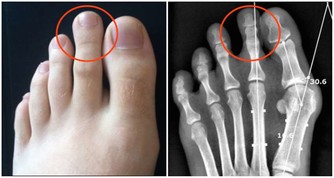

1932年的一項研究結果得出,改變飲食有助於改善蛀牙問題。研究人員得出結論,缺乏礦物質和脂溶性維生素以及過度攝取植酸與加工糖較易引起蛀牙。

根據《Remedy Daily》網站的報導,作家David Wolfe先生利用了1932年的研究,想出了以下5個有助於治療蛀牙的方法,一起來看看吧!